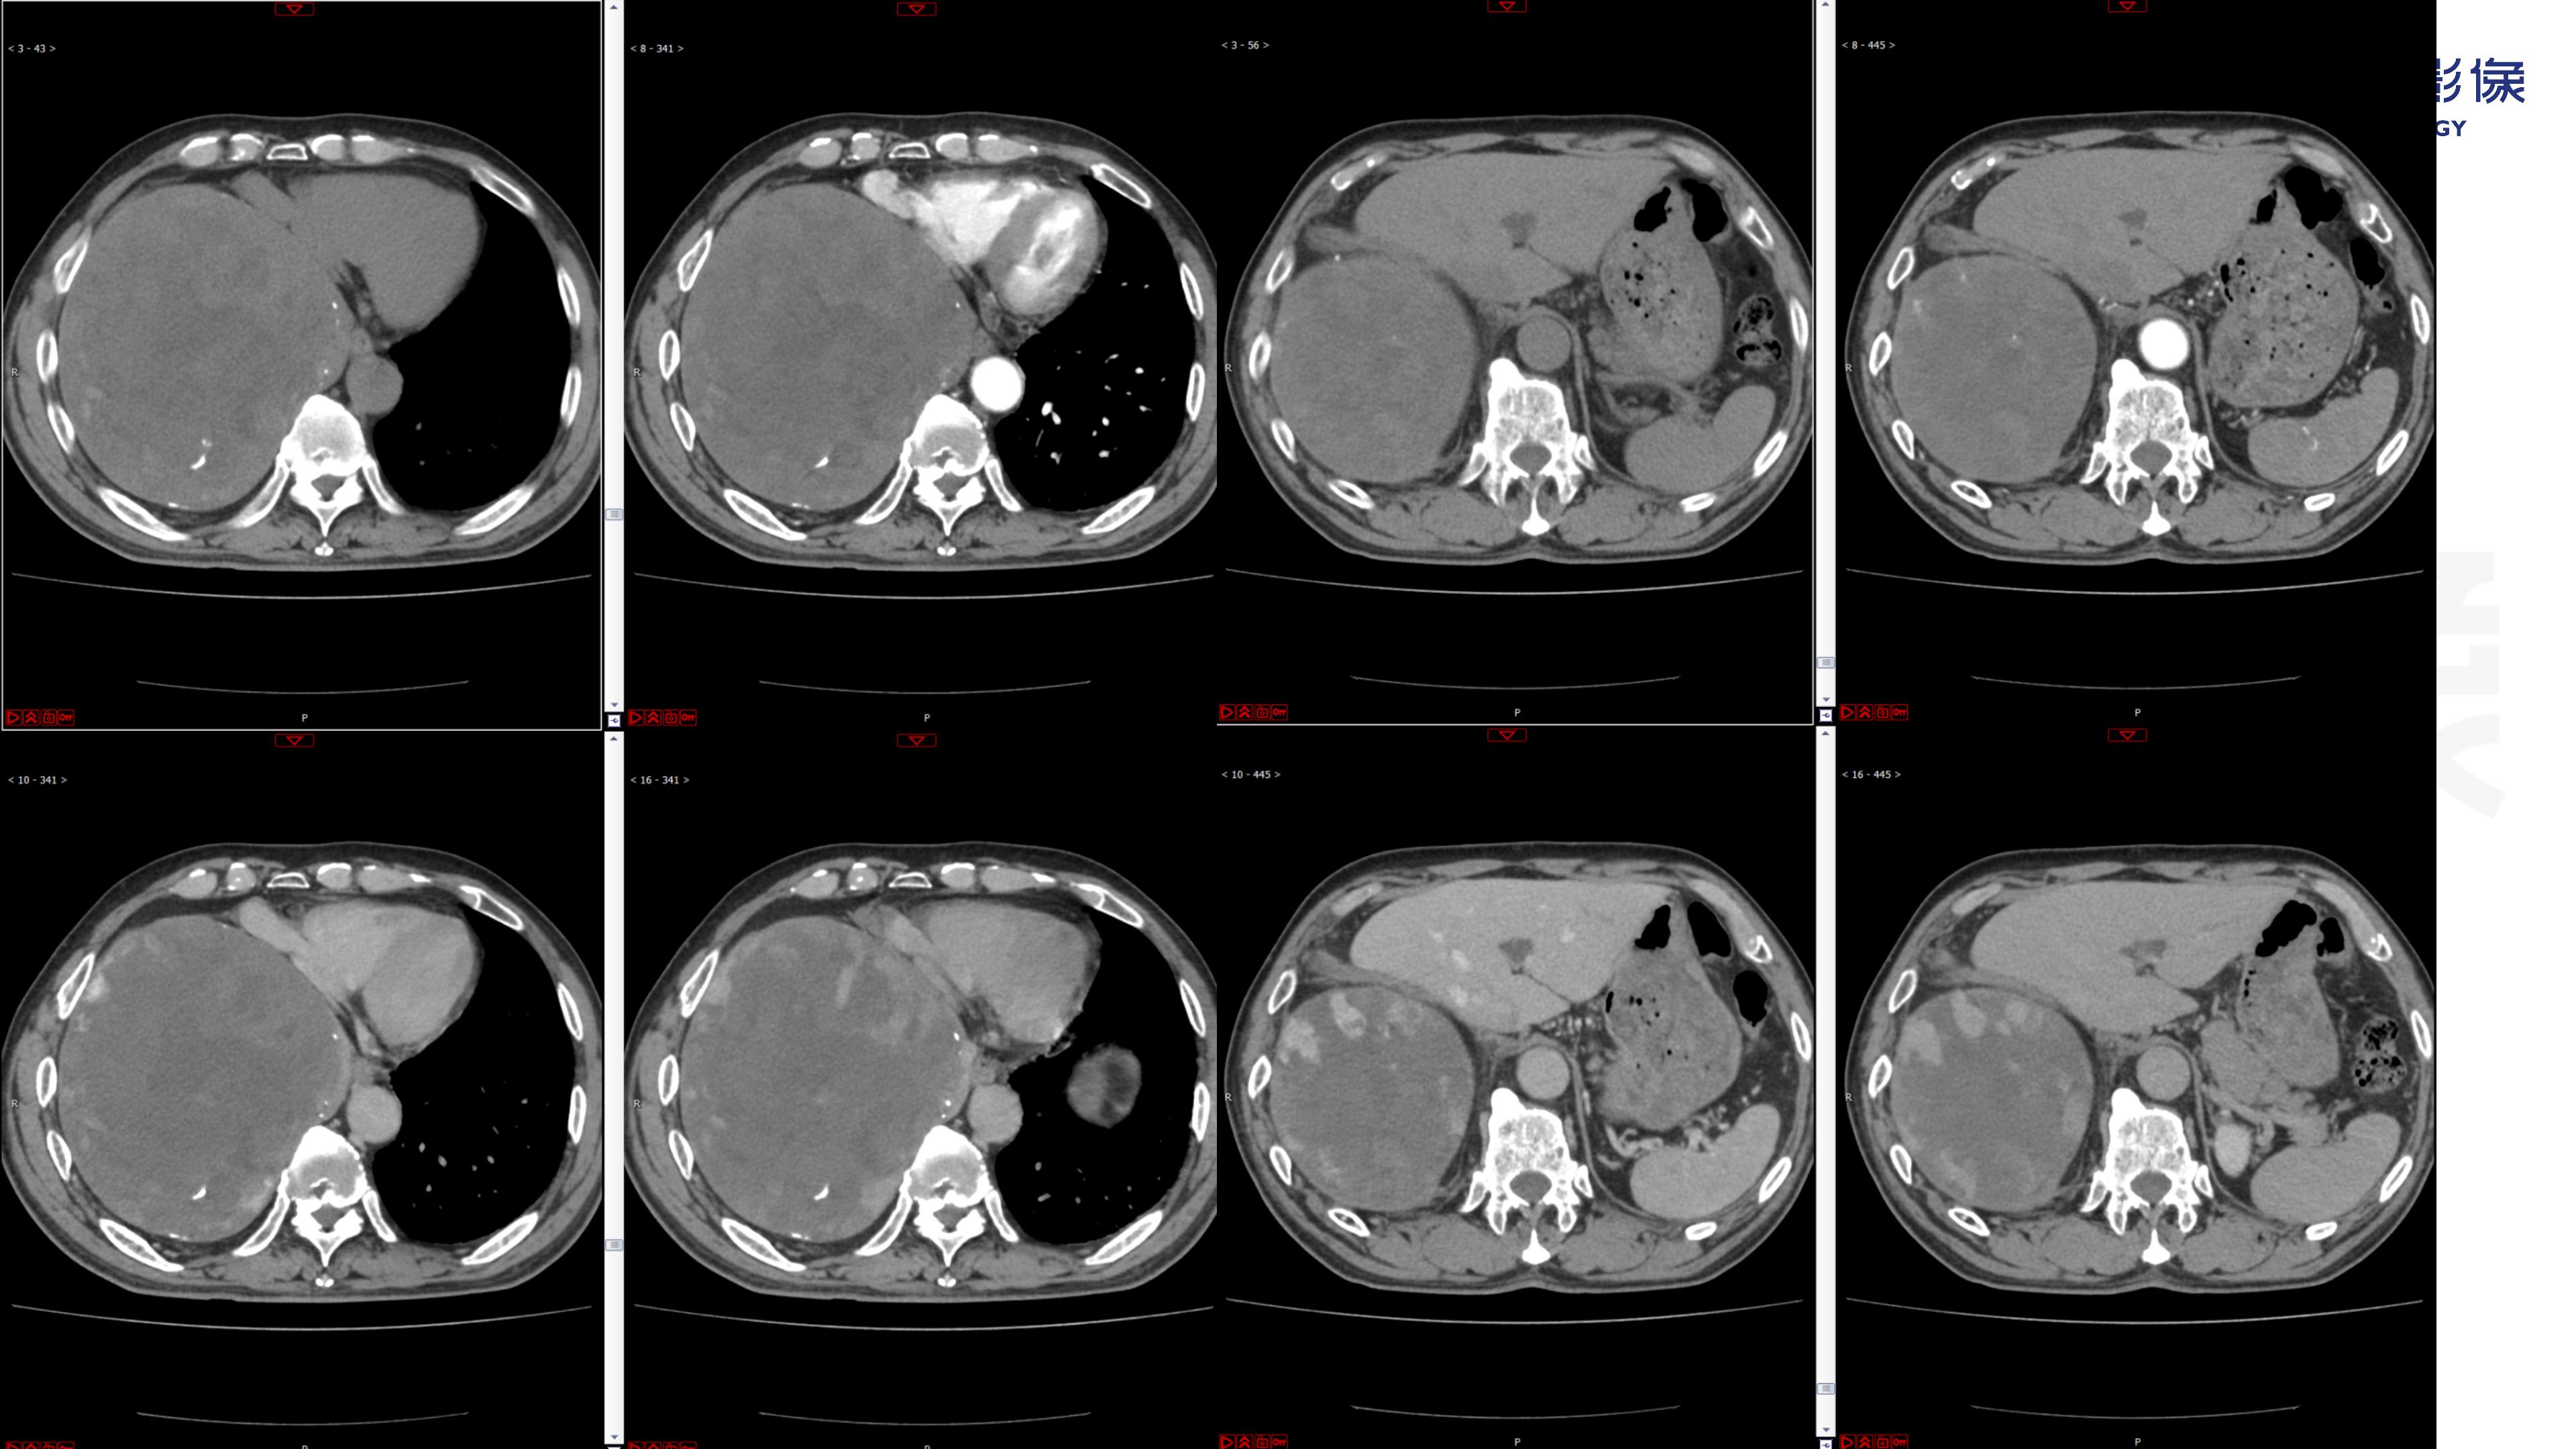

纵隔血管瘤-鼎湖社群读片病例